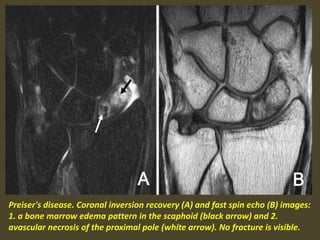

Preiser's disease. Coronal inversion recovery (A) and fast spin echo (B) images:

1. a bone marrow edema pattern in the scaphoid (black arrow) and 2.

avascular necrosis of the proximal pole (white arrow). No fracture is visible.

Idiopathic avascular necrosis of the scaphoid (Preiser’s disease)